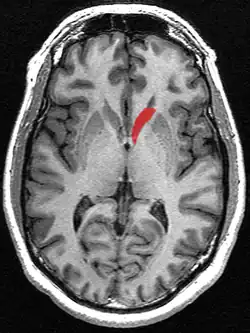

Transverse cut of brain (horizontal section), basal ganglia is blue | |

Along with the putamen, the caudate forms the dorsal striatum, which is considered a single functional structure; anatomically, it is separated by a large white-matter tract, the internal capsule, so it is sometimes also described as two structures—the medial dorsal striatum (the caudate) and the lateral dorsal striatum (the putamen). In this vein, the two are functionally distinct not because of structural differences, but merely because of the topographical distribution of function.

The caudate nuclei are near the center of the brain, sitting astride the thalamus. There is a caudate nucleus in each hemisphere of the brain. Each nucleus is C-shaped, with a wider "head" (caput in Latin) at the front, tapering to a "body" (corpus) and a "tail" (cauda). Sometimes a part of the caudate nucleus is called the "knee" (genu).[6] The caudate head receives its blood supply from the lenticulostriate artery; the tail of the caudate receives its blood supply from the anterior choroidal artery.[7]